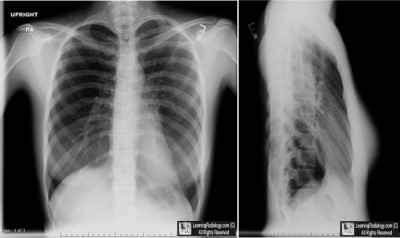

Case of the Week 531

What is the most likely diagnosis?

• 23 year-old with systolic ejection murmur

Frontal and Lateral Chest Radiographs

2. Straight Back Syndrome

Straight Back Syndrome

• Loss of normal kyphotic curve of thoracic spine associated with an abnormally short anterior-posterior dimension to the chest causing compression of the heart